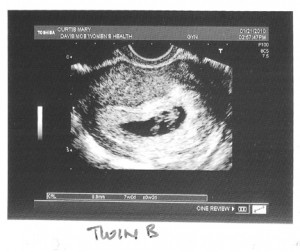

Before I go to sleep, I’ll post the first images and stats of our twins below – twin A (lower in the uterus) and twin B. Love you all!